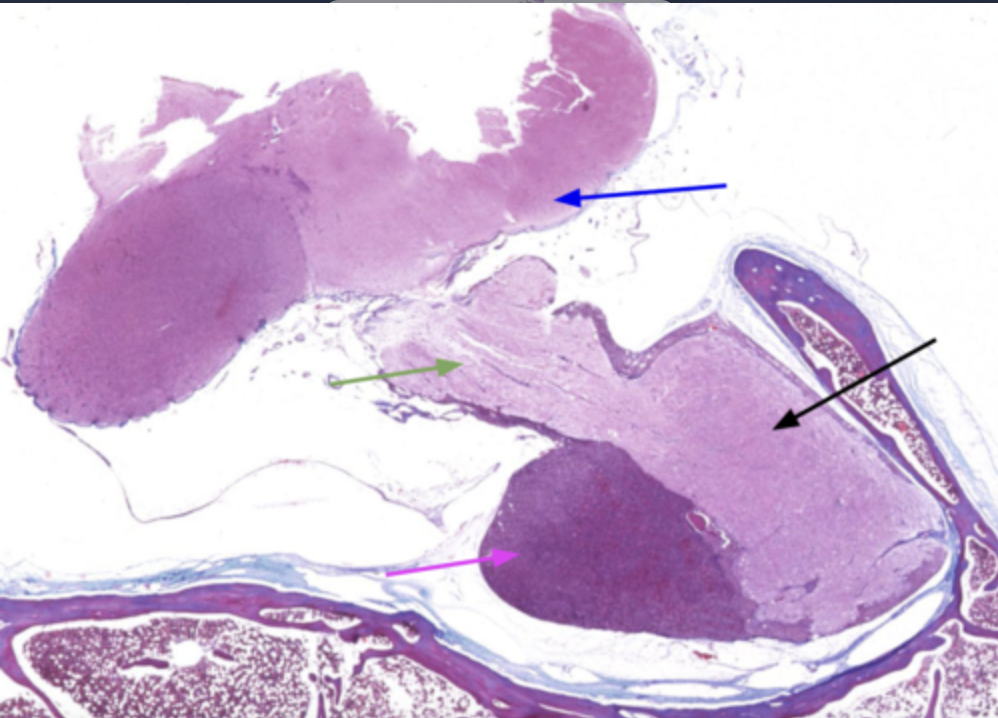

What is the magenta arrow pointing to?

adenohypophysis

What is the black arrow pointing to?

Neurohypophysis

The adenohypophysis is what in color when compared to the neurohypophysis

Darker in color

What is the green arrow?

Infundibulum

What is the blue arrow?

Hypothalamus